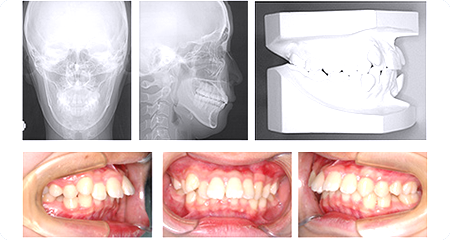

現在の不正咬合の状態を正確に把握するために、レントゲン撮影や顔写真、噛み合わせチェック、歯型採取などの精密検査を行います。

これらの結果をもとにより詳しい診断・矯正治療計画を立てます。

歯の模型や検査結果をもとに、患者様にあった矯正治療計画の詳細やなどについて、詳しい説明をいたします。